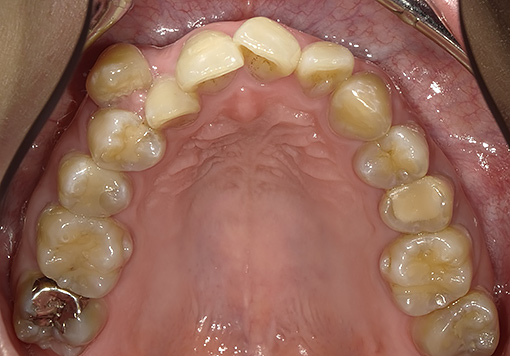

Case 03

before

after